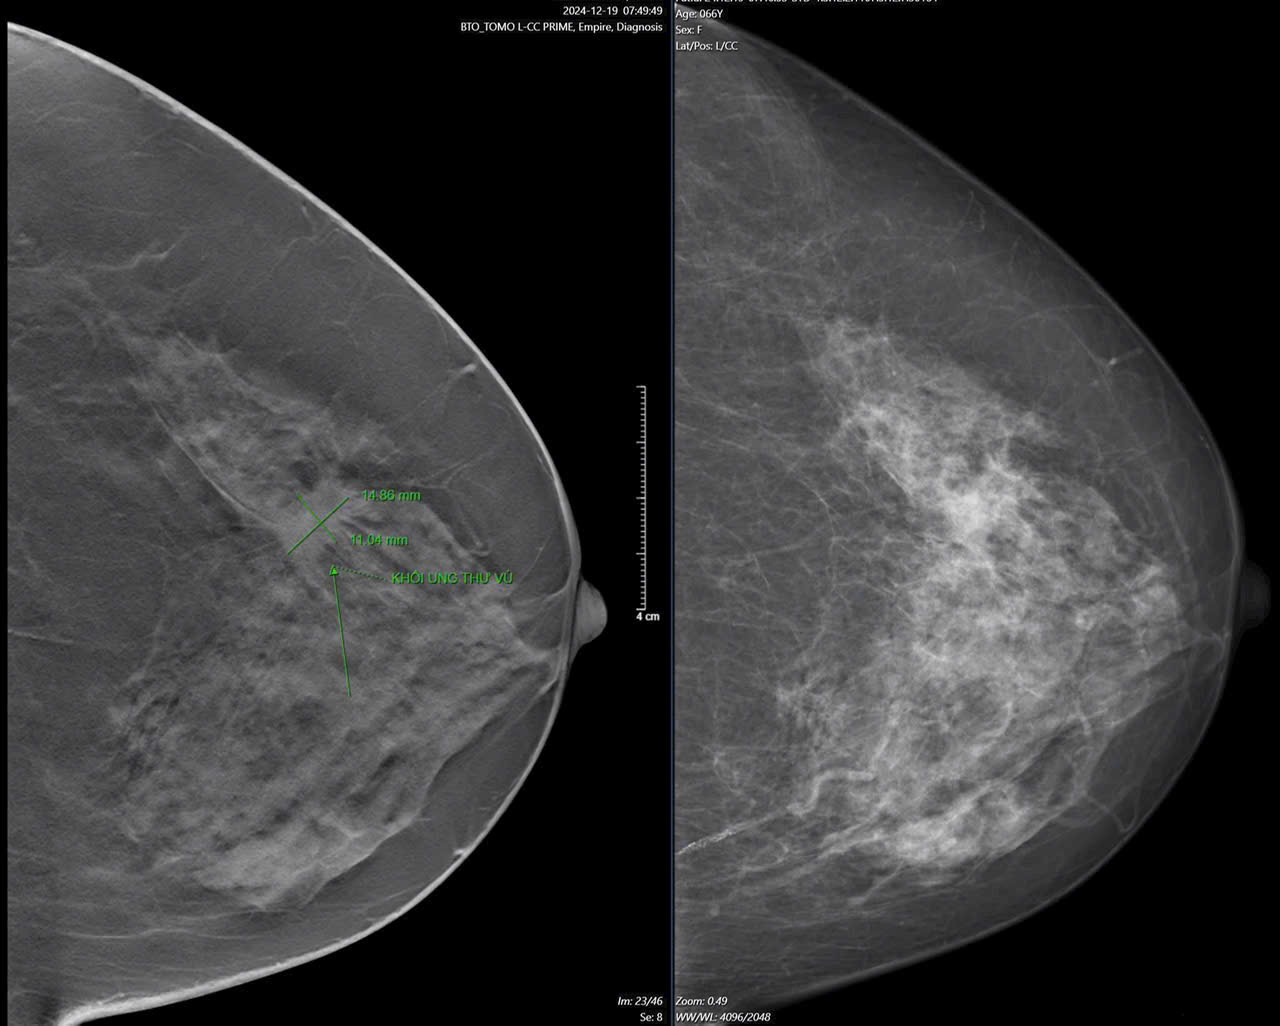

Bệnh nhân nữ 66 tuổi đến bệnh viện khám tim do loạn nhịp và cơn đau thắt ngực. Dù bác sĩ tim mạch kết luận chưa có vấn đề nghiêm trọng, nhưng bà vẫn cảm thấy bất an về sức khỏe, đặc biệt là ở vùng vú.

Không bỏ qua linh cảm của mình, bà quyết định đến Trung tâm Vú Mammocare để kiểm tra chuyên sâu. Và điều không ngờ đã xảy ra: bác sĩ phát hiện một khối u nhỏ chỉ 15mm – ung thư vú giai đoạn sớm.

Dù ung thư vú là điều không ai mong muốn, nhưng nhờ phát hiện kịp thời, bà có thể điều trị hiệu quả với phương pháp ít xâm lấn hơn. Nếu bỏ qua dấu hiệu ban đầu, bệnh có thể tiến triển sang giai đoạn nguy hiểm hơn.